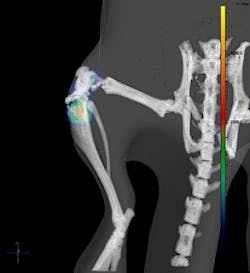

Co-registration allows researchers to overlay images from multiple imaging modalities, providing more comprehensive insight into the molecular and anatomical features of an animal and its biology. For example, optical imaging data, which may be used to identify and quantify tumor burden at the molecular level, can be integrated with microCT (x-ray micro computed tomography) data which provides complementary anatomical detail and morphological quantification.

With the Living Image Multi-Modality Software Module, researchers can directly import data from preclinical microCT, MRI, PET and SPECT into the Living Image software environment for combination with 3D bioluminescence and fluorescence images from an IVIS Spectrum optical imaging system. The software contains advanced visualization features, and the Mouse Imaging Shuttle immobilizes the animal for transport between the different systems to enable high-quality co-registration. The multi-modality kit has been optimized for use with Caliper's IVIS Spectrum and Quantum FX microCT imaging systems to enable comprehensive longitudinal imaging of a single animal over multiple time points without harming the subject. Living Image software is now uniquely capable of processing quantitative, functional optical data and integrating it with the anatomical views familiar to clinicians.